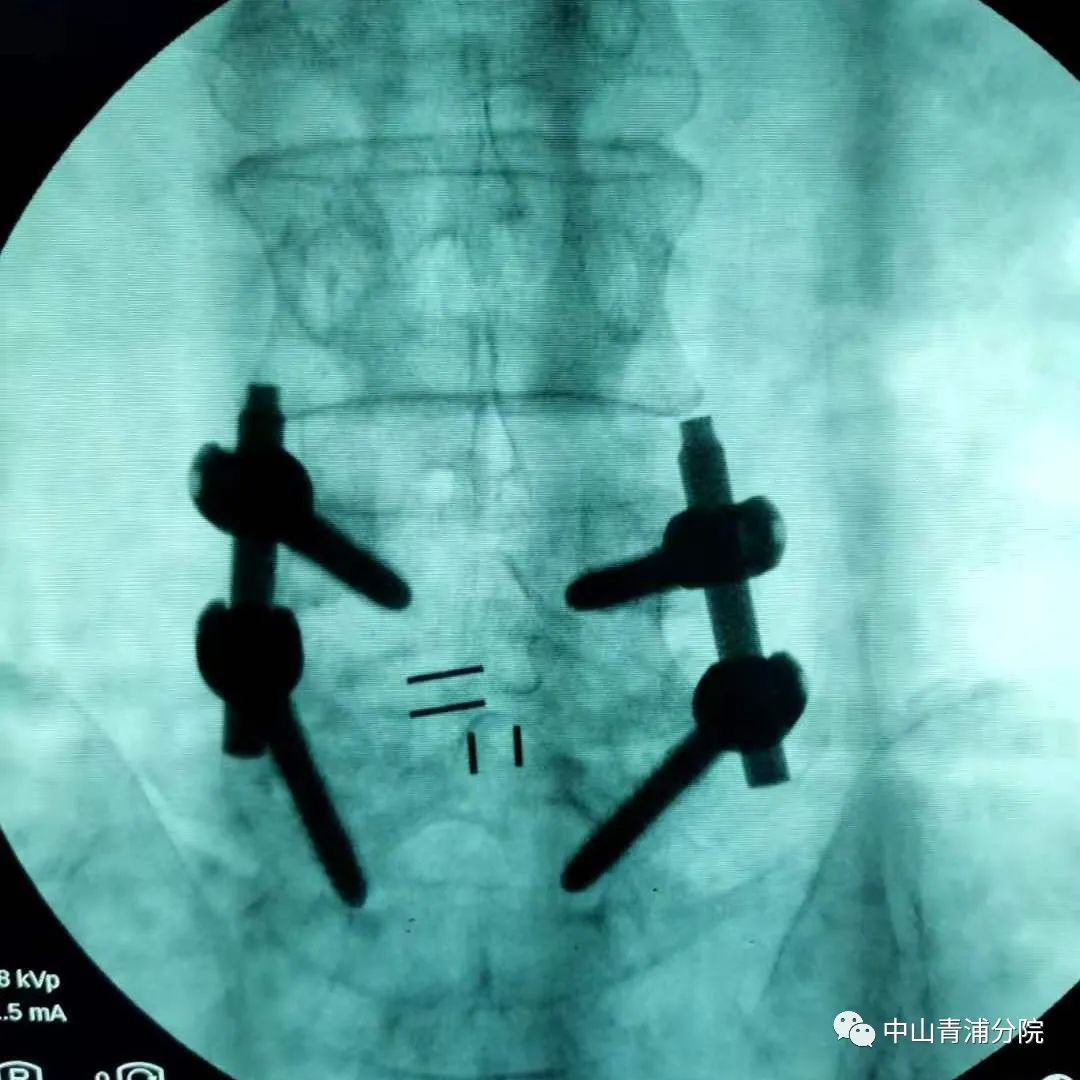

腰椎滑脱减压复位融合内固定手术目前在昌宁县人民医院尚未独立开展,此次骨科的高如锋副主任应邀来到昌宁为两位腰椎管狭窄和滑脱患者手术,同时也是手术示教,希望能将这种技术留在昌宁。